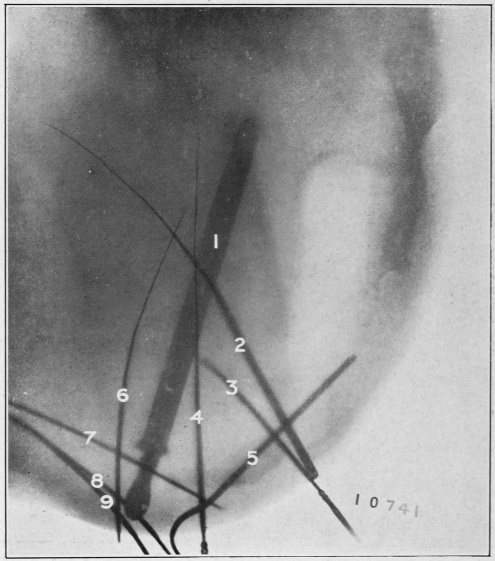

Nine Radiograph Illustrations Showing Mucus Channels and Cavities200

Rebellion of our outraged Internal Economy.